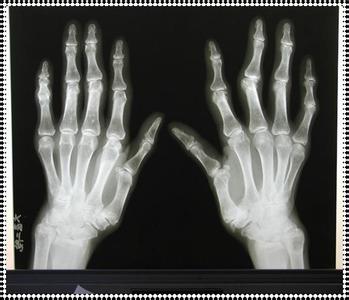

郑州治疗类风湿的医院哪家好?类风湿性关节炎患者怎么去做好护理呢

在我们生活的周边环境中有很多的人不喜欢阴沉的天气或者下雨的天气,因为这个时候他们的关节会感到很疼痛,这些人有可能已经患有了类风湿。这几年中,类风湿患有明显的增多了,类风湿性关节炎的患者应该怎么去做好相关措施呢?下面就是郑州类风湿医院专家为大家介绍的一些方法。